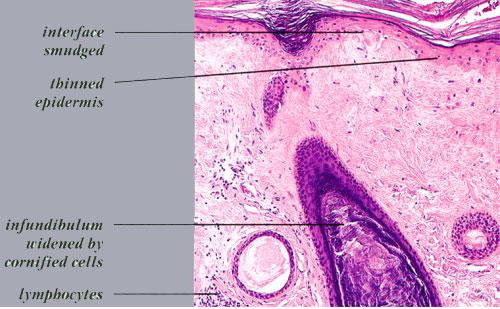

Read MoreAlopecia of Lichen Planus =الحاصة بسبب الحزاز المنبسط